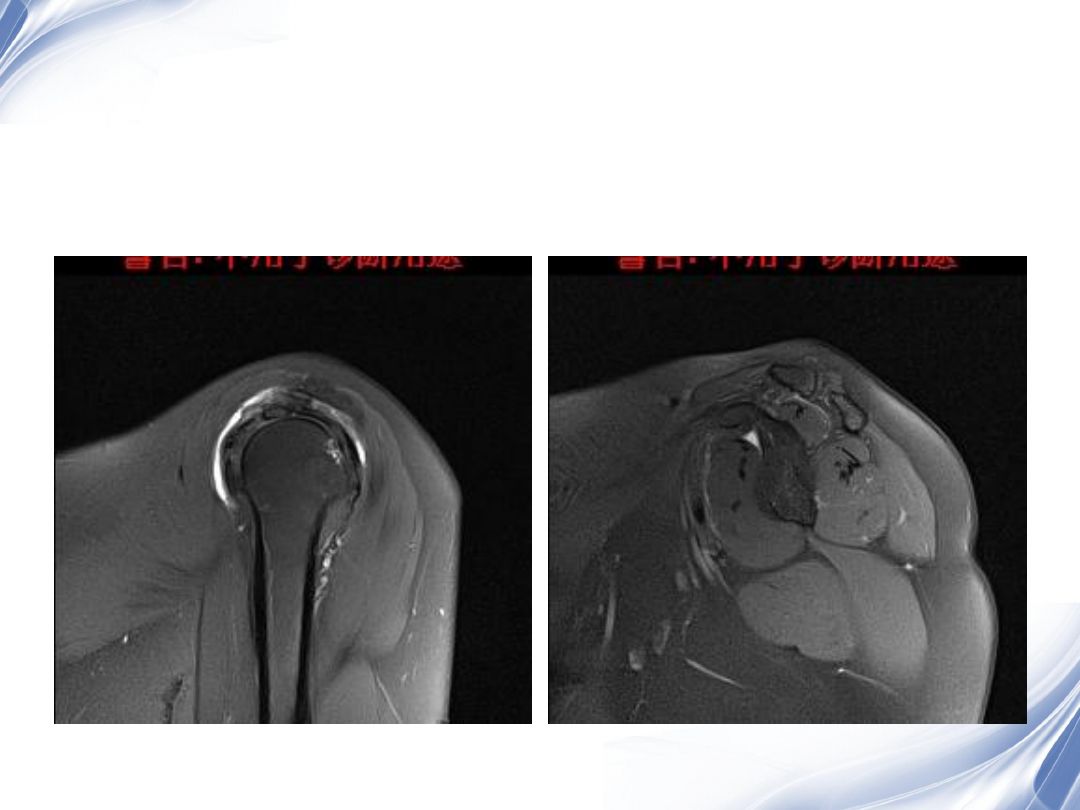

巨大肩袖损伤(冈上肌)

T2WI

T1WI

36

术后

2

37